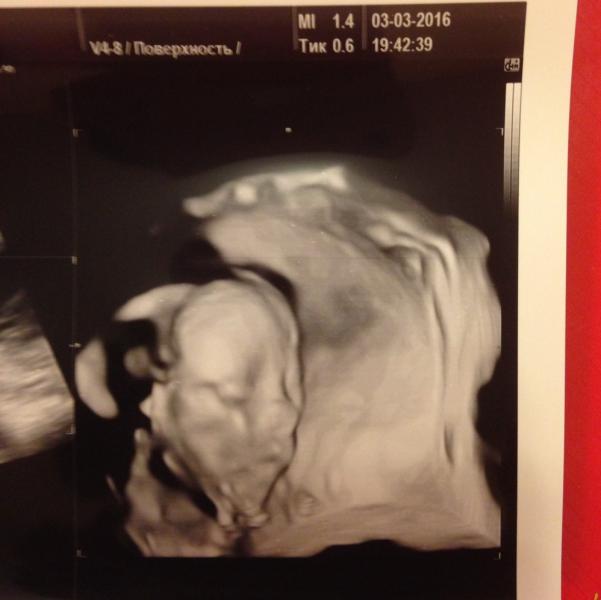

Вчера прошёл наш второй скрининг,делали опять же в #ПраймРоуз у #Баженовой 👍🏽 наша девочка осталась девочкой 100% 😍🎀👏🏽💗💜💖 Поля на весь экран показала свой пирожок и у нашего папы сразу все надежды на писюн пропали 😂 Так же как и на первом УЗИ мы опережаем почти на неделю, поэтому ПДР ставят не на 16 как по месячным, а на 11 июля 🙏🏽 Счастье наше весит 413 грамм и 22 см 🙈 Все хорошо, мы обе здоровы 😌 Закрывалась ручками,вытягивала ножки и пила водичку почти все УЗИ 😍❤️ Людмила Николаевна сказала пока...